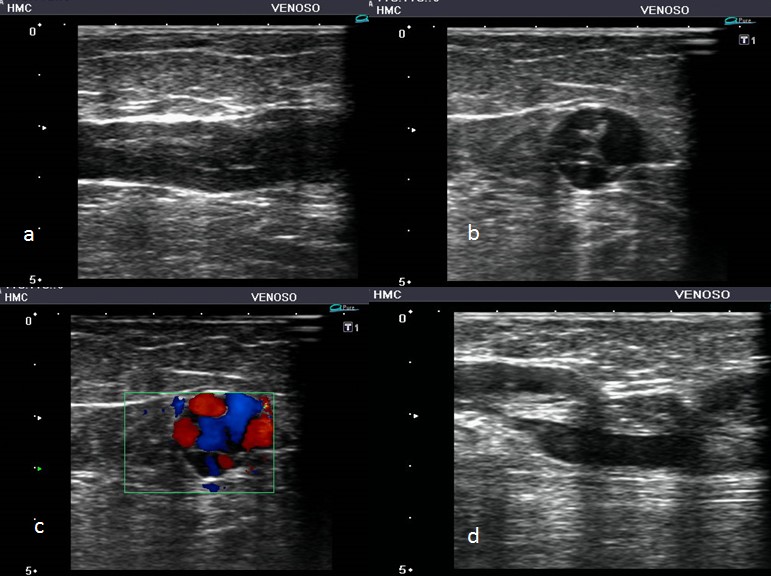

Para comprender la insuficiencia venosa es necesario conocer la fisiología. Un componente fundamental en la anatomía de las venas lo constituyen las válvulas venosas, que son pliegues de colágeno en forma de semiluna recubiertas de endotelio que salen de la pared de la vena. Presentan dos valvas, llamadas “cúspides”, con dos bordes libres hacia la porción medial de la vena (Fig. 10).

Las válvulas son más numerosas en la pierna distal y disminuyen hacia la cadera. En las extremidades inferiores, las válvulas funcionan para dividir la columna hidrostática de la sangre en segmentos, y para asegurar el flujo de superficial a profundo y de caudal a craneal. Las cúspides de la válvula de las extremidades inferiores permanecen abiertas durante el reposo en posición supina. El cierre de la válvula es un evento iniciado por inversión pasiva del gradiente de presión transvalvular anterógrada en reposo.

A medida que el gradiente de presión se invierte, hay un corto período de flujo retrógrado, o reflujo, hasta que el gradiente se hace suficiente para causar el cierre de la válvula. Por lo tanto, el cierre de la válvula requiere, primero, el cese de flujo anterógrado, seguido de un breve intervalo de flujo retrógrado de velocidad suficiente para coaptar completamente las cúspides (Fig.11) (16). En condiciones de normalidad valvular, con la persona en posición vertical, el reflujo dura menos de 0,5 segundos (Fig. 12), y si este persiste más de 0,5 segundos se define como “reflujo patológico” (Fig. 13).